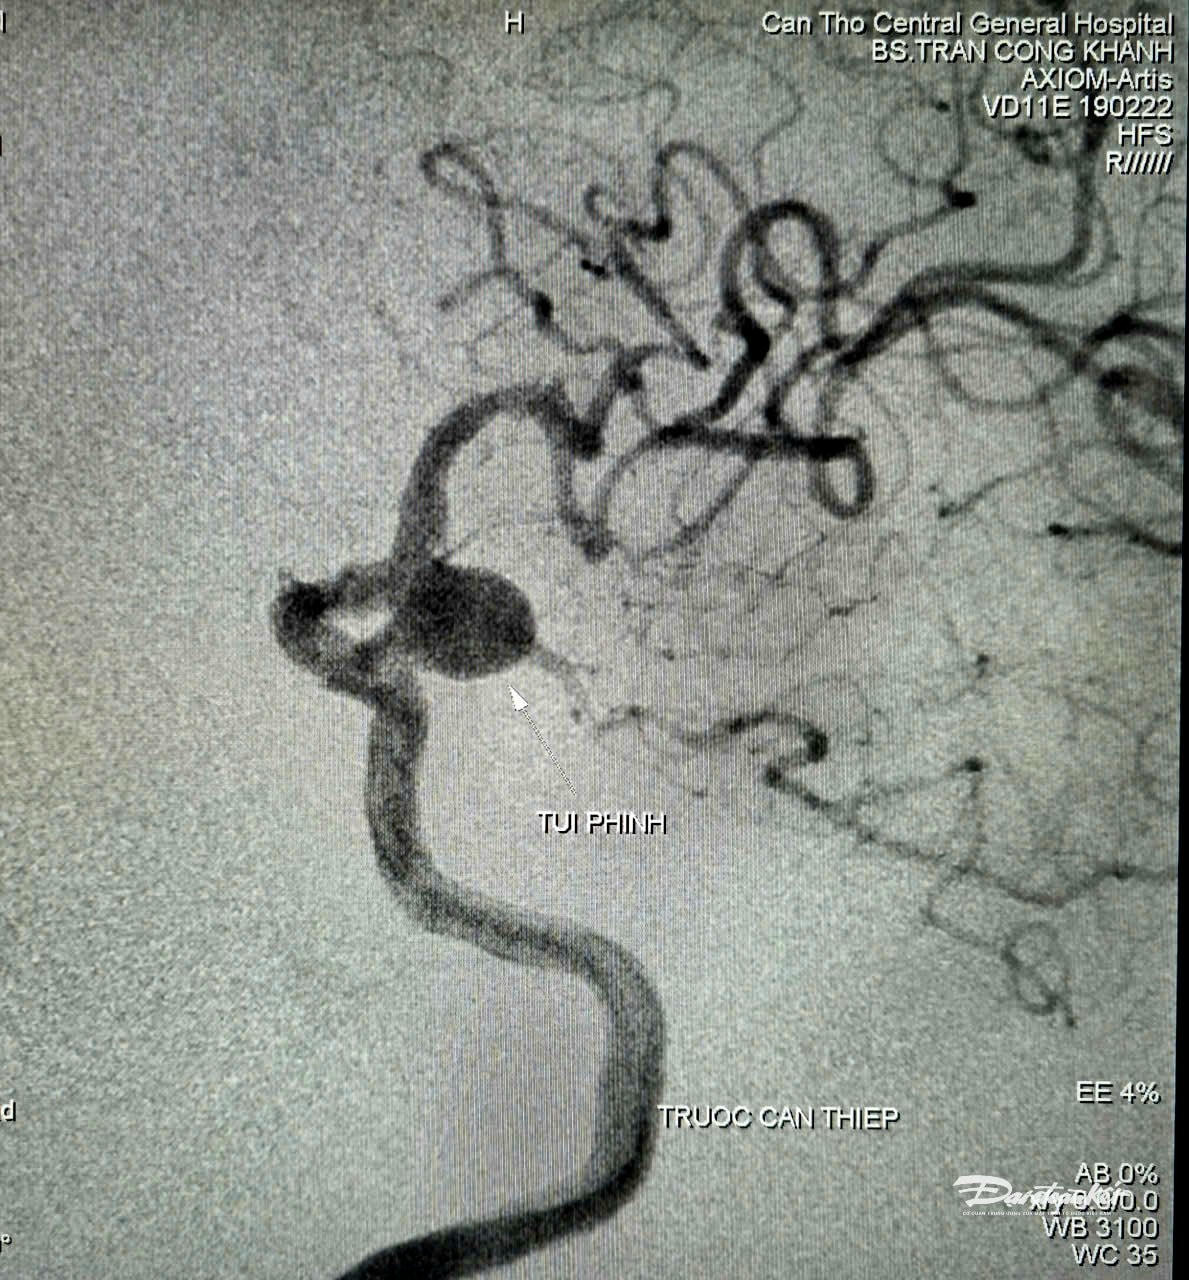

Kết quả chụp cắt lớp vi tính và cộng hưởng từ cho thấy nhiều tổn thương cũ vùng não, túi phình đoạn gốc động mạch cảnh trong - thông sau bên trái, kích thước 9,2mm x 12mm, túi phình đang phát triển qua thời gian theo dõi (nguy cơ vỡ trong 5 năm khoảng 17.8%, ước lượng theo thang điểm PHASE 12 điểm).

Sau khi hội chẩn đa chuyên khoa và dựa trên các khuyến cáo, cân nhắc, ê-kíp quyết định tiến hành chụp mạch số hóa xóa nền (DSA) và can thiệp nội mạch nút túi phình, giúp bệnh nhân hạn chế nguy cơ vỡ gây đột quỵ, xuất huyết.

Các bác sĩ đã luồn vi ống thông siêu nhỏ đến vị trí túi phình và tiến hành thả 4 vòng xoắn kim loại (coils) vào trong lòng túi phình. Kết quả chụp kiểm tra ghi nhận: túi phình làm tắc gần hoàn toàn, dòng máu lưu thông ổn định.